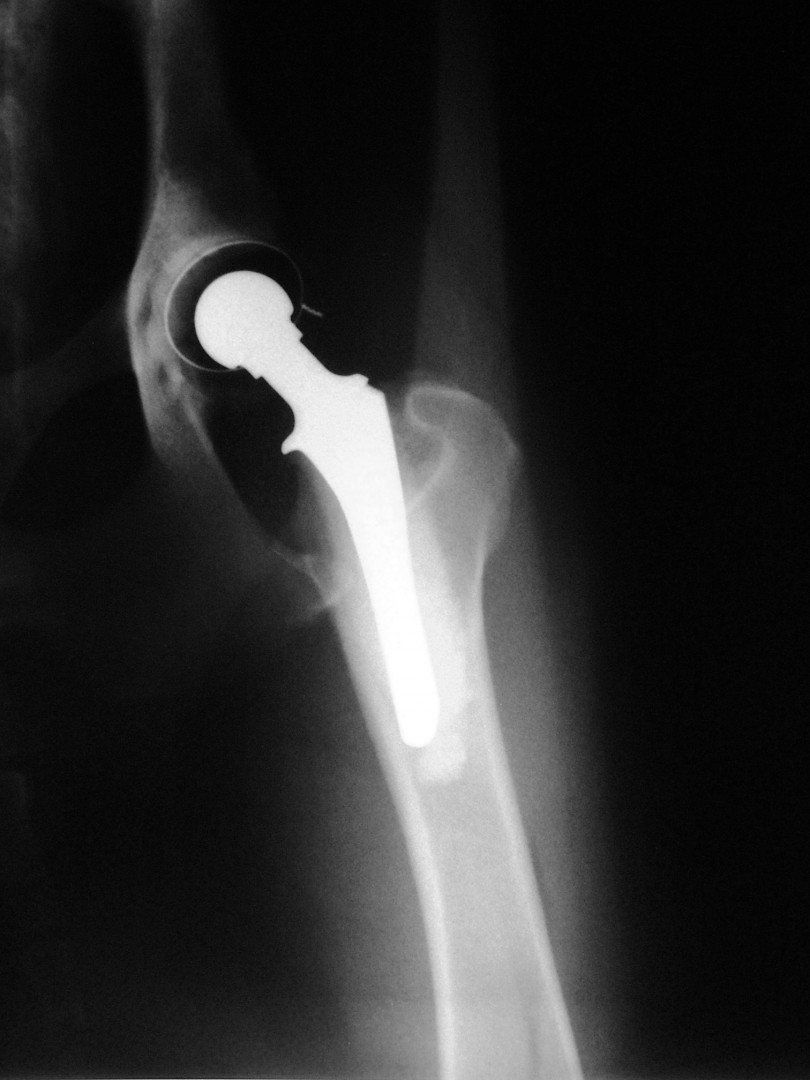

Bár a csípőízület megbetegedéseiről – mint a leggyakrabban tárgyalt ortopédiai megbetegedésről- első körben nem szerettem volna szólni, mégis megteszem, mert 2010. májusában egy hosszabb egyeztetést és szervezést követően beültettük az első teljes csípőízületi protézist…

A szervezés két részből állt: egyrészt felkerestük azt a magyarországi gyártót, aki a hazai anyagi lehetőségeket is figyelembe véve a szakmai szempontból is optimális rendszert le tudja gyártani, másrészt rábeszéltem Kendik Zsolt kollégámat, aki a hazai csípőízületi protézis beültetésének úttörője, hogy legyen segítségemre a műtét technikájának elsajátításában.

A tényleges műtét előtt temérdek teendő akad. A kutya teljes belgyógyászati kivizsgálása, egyéb ortopédiai és/vagy neurológiai betegségek kiszűrése, a tulajdonosokkal folytatott többszöri megbeszélés, a kockázatok mérlegelése és ezek részletes ismertetése jelentős energiát emészt fel. De ezek nélkül a beteg állat tulajdonosa nem tud reális döntést hozni: vállalható-e a műtét vagy sem?A műtéti időpont egyeztetése sem egyszerű: az operáció során 4 ember összehangolt munkájára, tökéletes aneszteziológiára és a műtétet követően az asszisztensek gondos munkájára van szükség a teljes gyógyuláshoz. Ez szintén jelentős szervezést igényel. A műtétet követő 10 napos kórházi ápolás és az ez utáni 3 hónapon át tartó szigorú mozgáskorlátozás betartása és betartatása a gyógyulás elengedhetetlen feltétele. Egy fiatal, ereje teljében lévő, energikus kutyánál ez néha nehezebb feladat, mint maga az operáció.

Az első műtét remekül sikerült és Connor, a skót juhász kutya megkapta a bal oldali új csípőízületét. A 7 napi kórházi tartás is problémamentesen zajlott és a varratszedés idejére a műtött végtag terhelése gyakorlatilag hibátlan volt. Az 1 hónapos és a 3 hónapos kontroll RTG vizsgálatokon sem jelentkezett szövődményre utaló jel, az 1 éves postoperatív időszakban már csak az látszott, hogy a műtött lábát jobban terheli, mint a nem operált végtagot. Így 2011. júniusában – immár sokadik csípőízületi protézis műtétként- a jobb oldali csípőízületét is megoperáltuk. Connor gyakorlatilag azóta teljes életet él és vidáman játszik társaival, még birkákat is terel…A majd két éves, a protetizálás során szerzett tapasztalatok azonban nálunk is hozzák a szakirodalomban leírt szövődményi lehetőségeket és arányokat. Leggyakrabban a beültetett protézis ficamával találkoztunk, de akadt sajnos kilökődési reakció is. Ezen problémák – az előzetes tájékoztatás ellenére is- mindig váratlanul érik a tulajdonost és az állatorvost egyaránt. Megoldásuk szinte kizárólag műtéti, ami újabb kockázatot, újabb fizikai és anyagi áldozatot jelent.